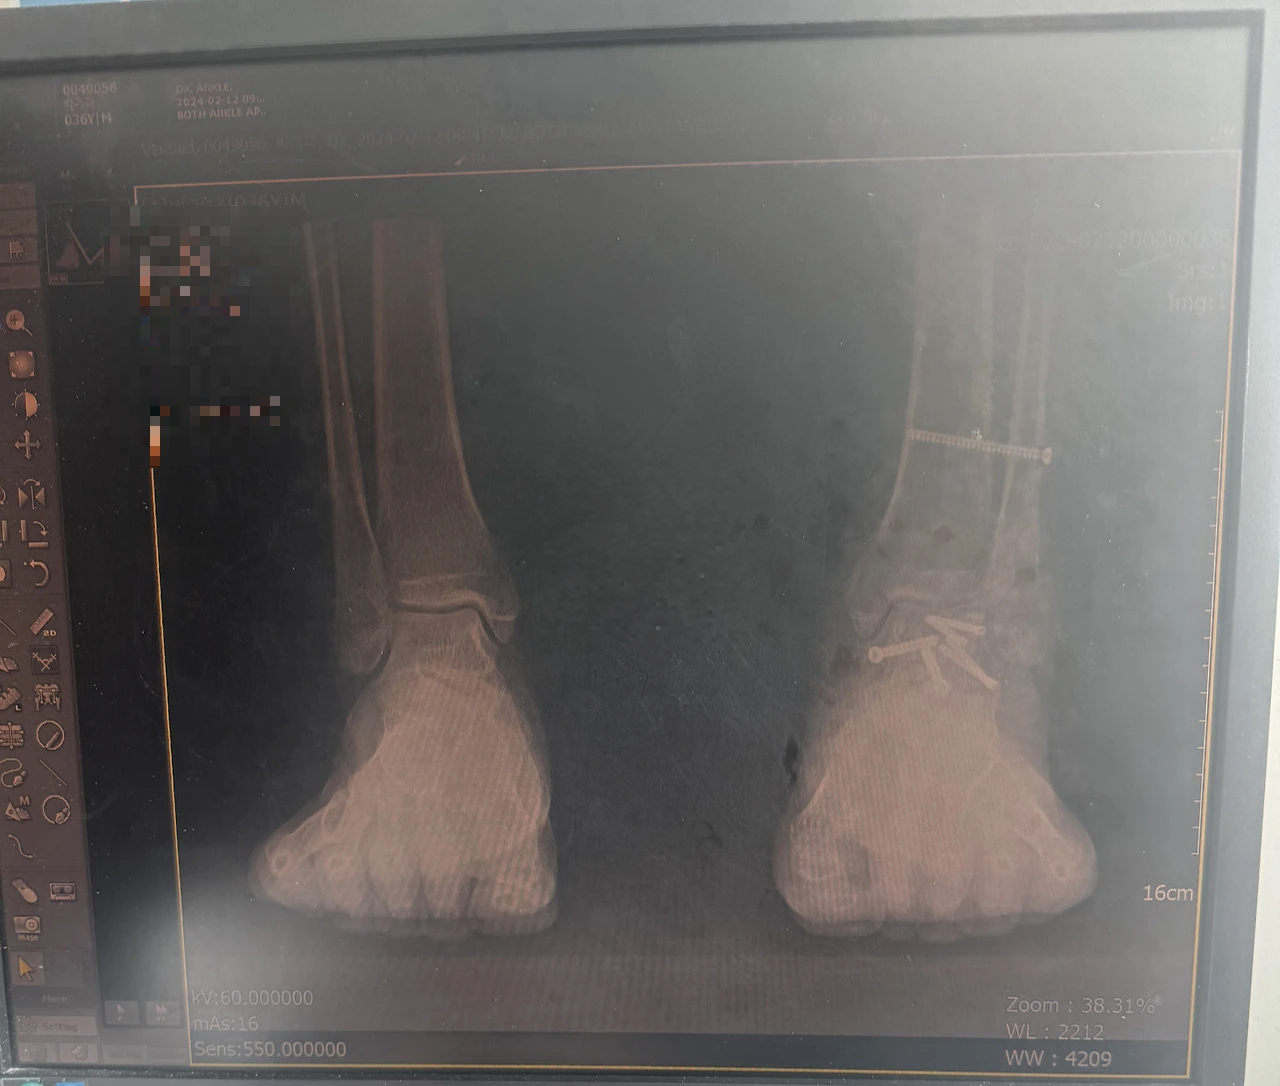

IMG_1686.HEIC 정강이 핀제거 전

정기검진이 있는 날마다 의사 선생님께 불편함을 호소하였다. 의사 선생님은 인대가 움직이지 않도록 정강이 뼈 2개를 고정한 나사를 제거하는 수술을 하지고 하셨다. 이 나사를 제거하면 각도가 더 나올 수 도 있다고 하셨다. 나는 그렇게 하겠다고 하고 수술 날짜를 잡았다. 수술은 1박 2일의 일정으로 간단하게 진행되었다. 그렇지만 척추마취와 수면 마취는 피할수가 없었다. 수술방에서 의사 선생님이 발목을 더 잘 움직일 수 있도록 꺾어서 풀어주셨다고 했다. 하지만 걸으면 압력 때문인지 발목의 각도는 이전처럼 안 나오기는 마찬가지였다. 의사 선생님이 현시점에서 할 수 있는 것은 다 했다고 하셨다.